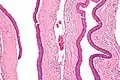

Odontogenic keratocysts have a diagnostic histological appearance. Under the microscope, OKCs vaguely resemble keratinized squamous epithelium;[14] however, they lack rete ridges and often have an artifactual separation from their basement membrane.[2]

The fibrous wall of the cyst is usually thin and uninflamed. The epithelial lining is thin with even thickness and parakeratinised with columnar cells in the basal layer which have focal reverse polarisation (nuclei are on the opposite pole of the cell).[12] The basal cells are an indication of the odontogenic origin as they resemble pre-ameloblasts. The epithelium can separate from the wall, resulting in islands of epithelium. These can go on to form 'satellite' or 'daughter' cysts, leading to an overall multilocular cyst.[9] Presence of daughter cysts is particularly seen in those with NBCCS.[12] Inflamed cysts show hyperplastic epithelium which is no longer characteristic of OKCs and can have resemblance to radicular cysts instead. Due to areas of focal inflammation, a larger biopsy is required for correct diagnosis of odontogenic keratocysts.[9]

High magnification of an odontogenic keratocyst.